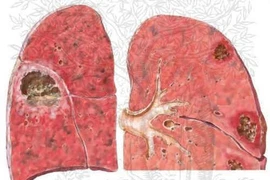

p xe phổi là tổn thương mưng mủ ở phổi rất dễ gây biến chứng nhiễm khuẩn huyết. Nếu không chữa khỏi có thể dẫn tới vỡ khối áp xe gây viêm màng phổi, màng tim, trung thất, hoại thư phổi…